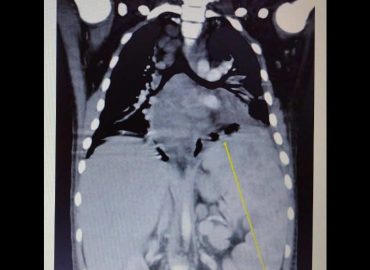

Paciente de 37 años, gestante, concurre a consulta obstétrica y se visualiza como hallazgo hepatomegalia y multiples nódulos hepáticos a […]